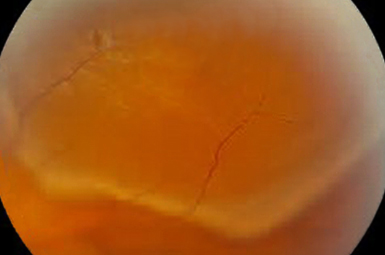

Retinal Detachment

This potentially blinding condition requires prompt surgical intervention. Successful reattachment usually preserves or restores visual function.